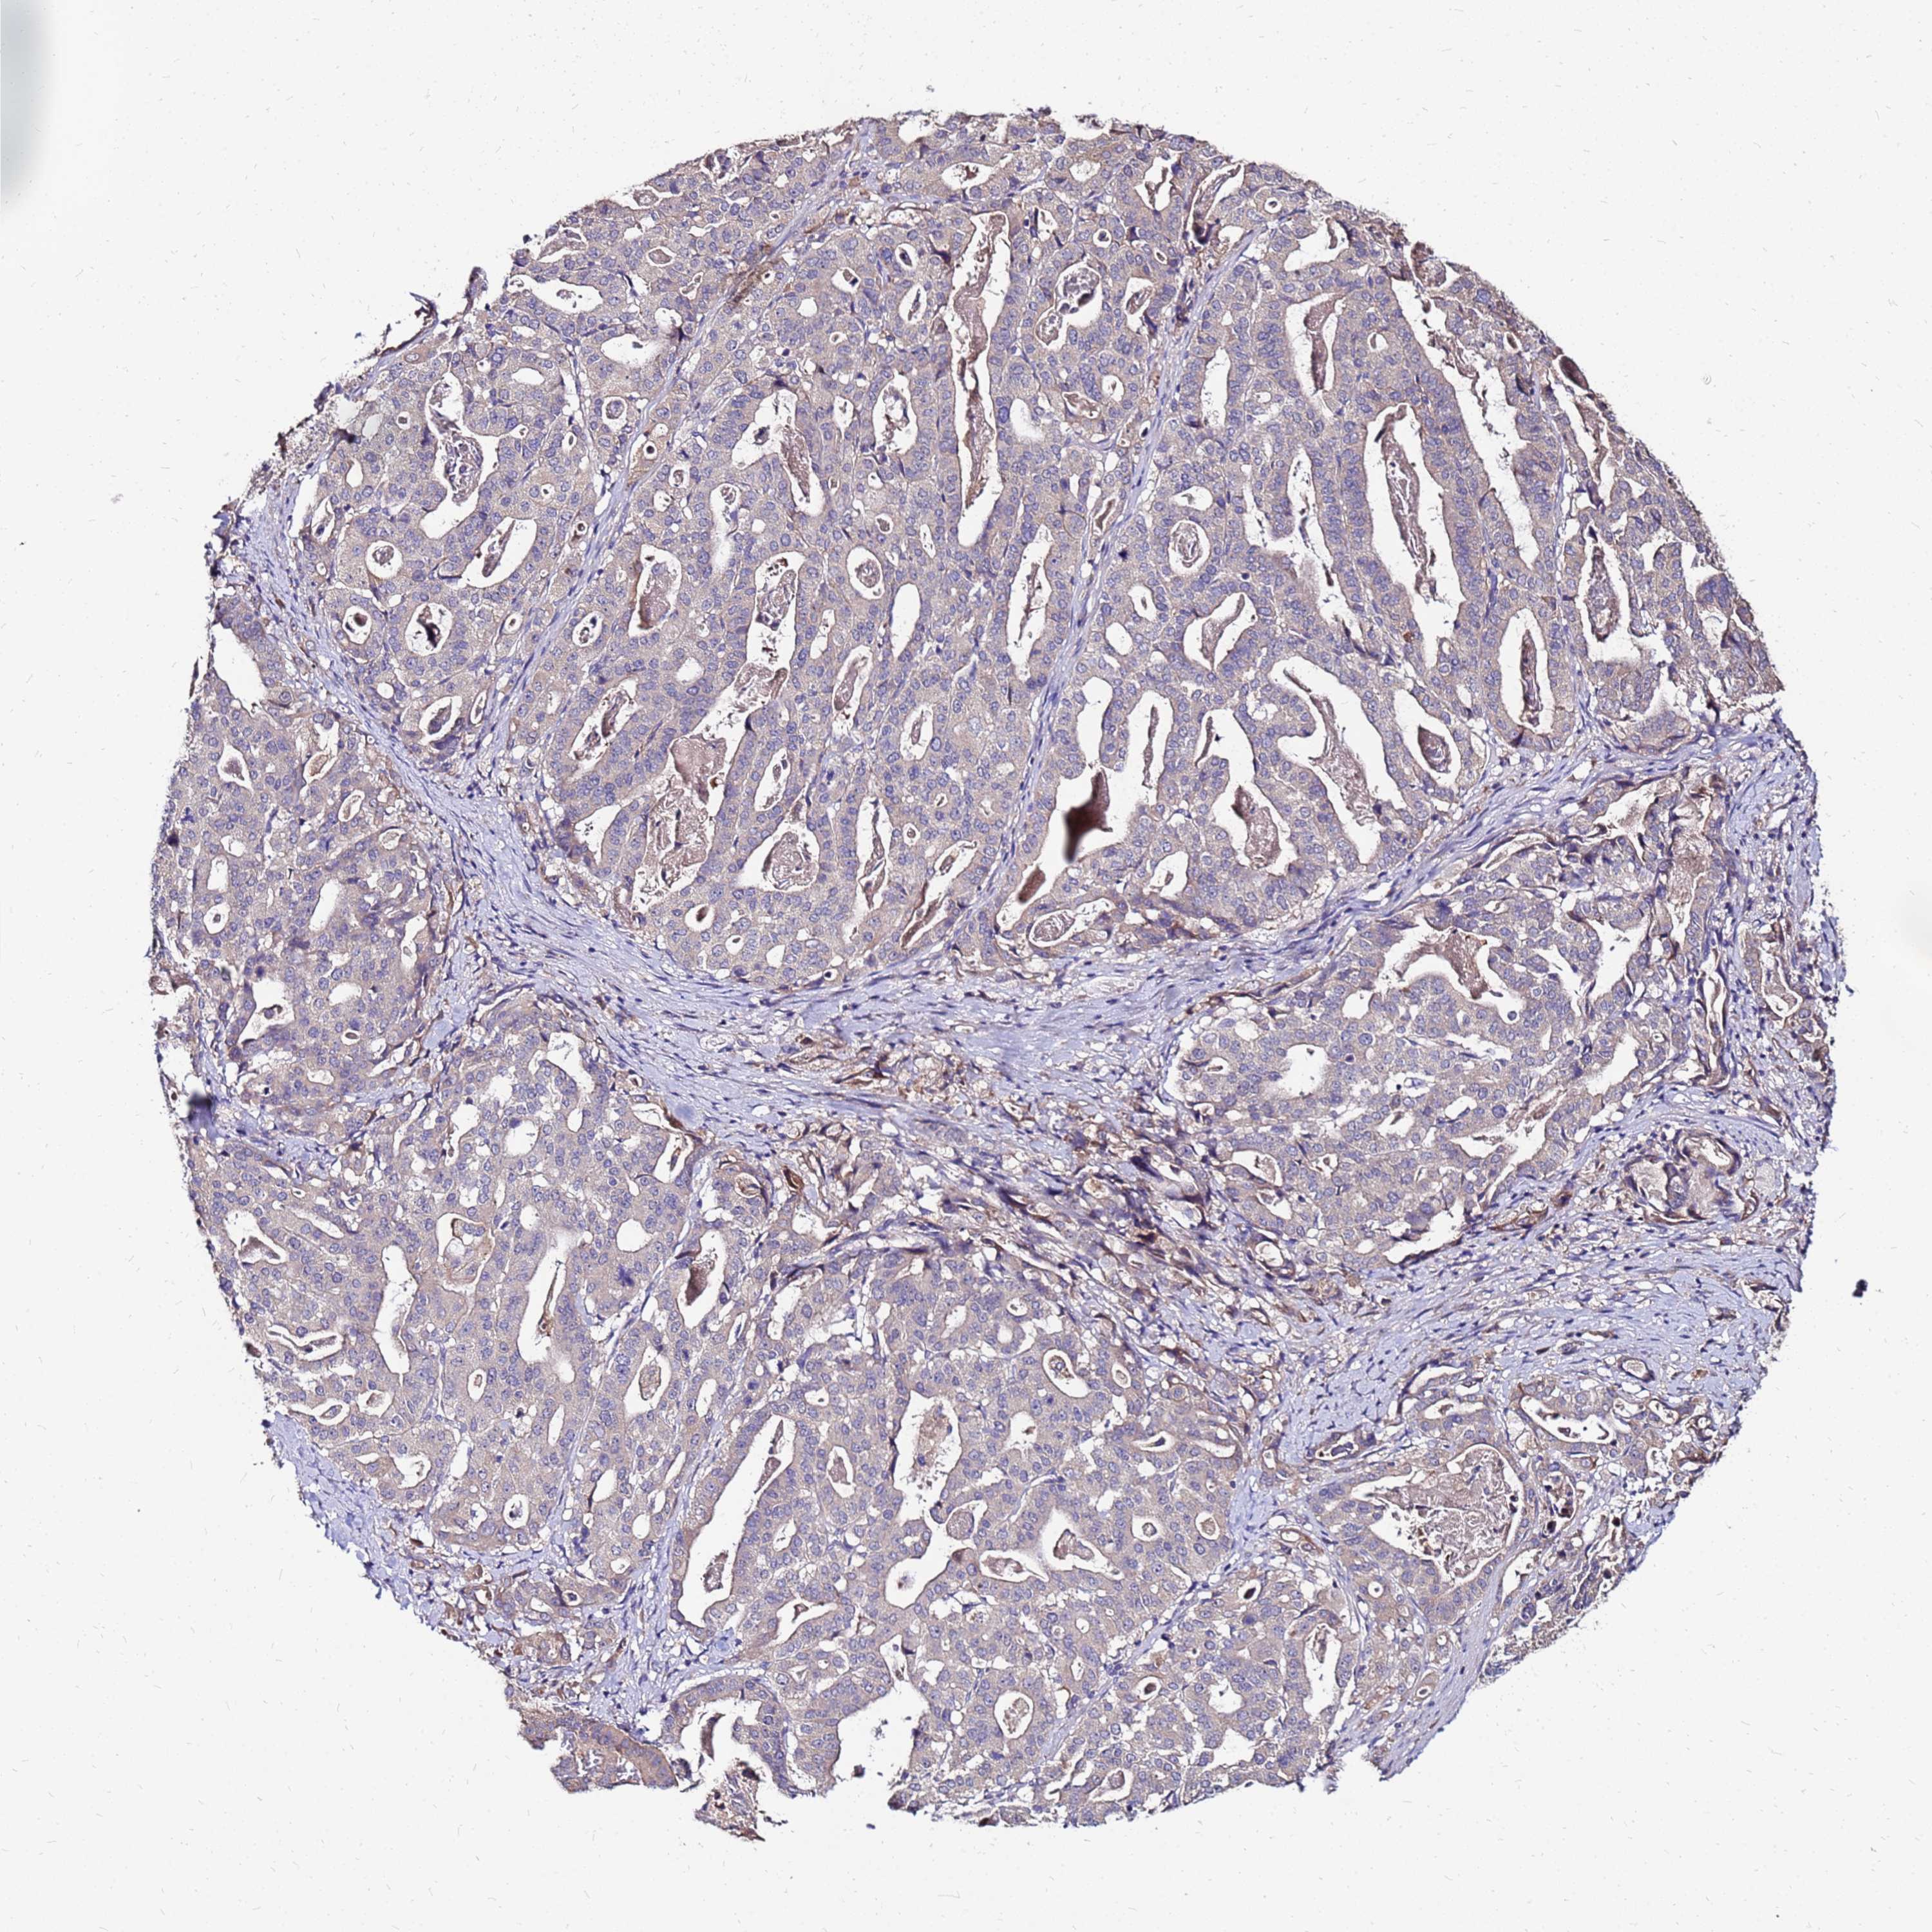

STOMACH CANCER - Protein expressioni

A mouse-over function shows sample information and annotation data. Click on an image to view it in a full screen mode. Samples can be filtered based on level of antibody staining by selecting one or several of the following categories: high, medium, low and not detected. The assay and annotation is described here.

Note that samples used for immunohistochemistry by the Human Protein Atlas do not correspond to samples in the TCGA dataset.

Antibody stainingi

Antibody staining in the annotated cell types in the current human tissue is reported as not detected, low, medium, or high, based on conventional immunohistochemistry profiling in selected tissues. This score is based on the combination of the staining intensity and fraction of stained cells.

Each image is clickable and will lead to virtual microscopy that enables deeper exploration of all samples and also displays staining intensity scores, fraction scores and subcellular localization as well as patient and tissue information for each sample.

Antibody HPA044188

Antibody HPA045619

Antibody HPA045699

Staining

High

Medium

Low

Not detected

Intensity

Strong

Moderate

Weak

Negative

Quantity

>75%

75%-25%

<25%

None

Location

Nuclear

Cytoplasmic/membranous

Cytoplasmic/membranous,nuclear

Adenocarcinoma, NOS